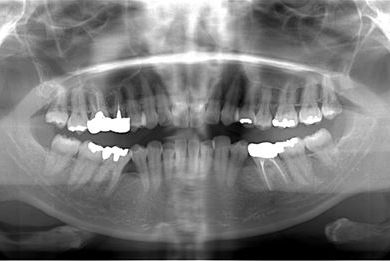

性別/年齢 女性 / 39歳

主訴 上の前歯の歯並びが気になる。

治療方針 セラミック治療により、審美的回復を行う。

治療内容 オールセラミッククラウン2本(オールセラミック用土台2本)

総治療費 301,875円

治療期間 2ヶ月